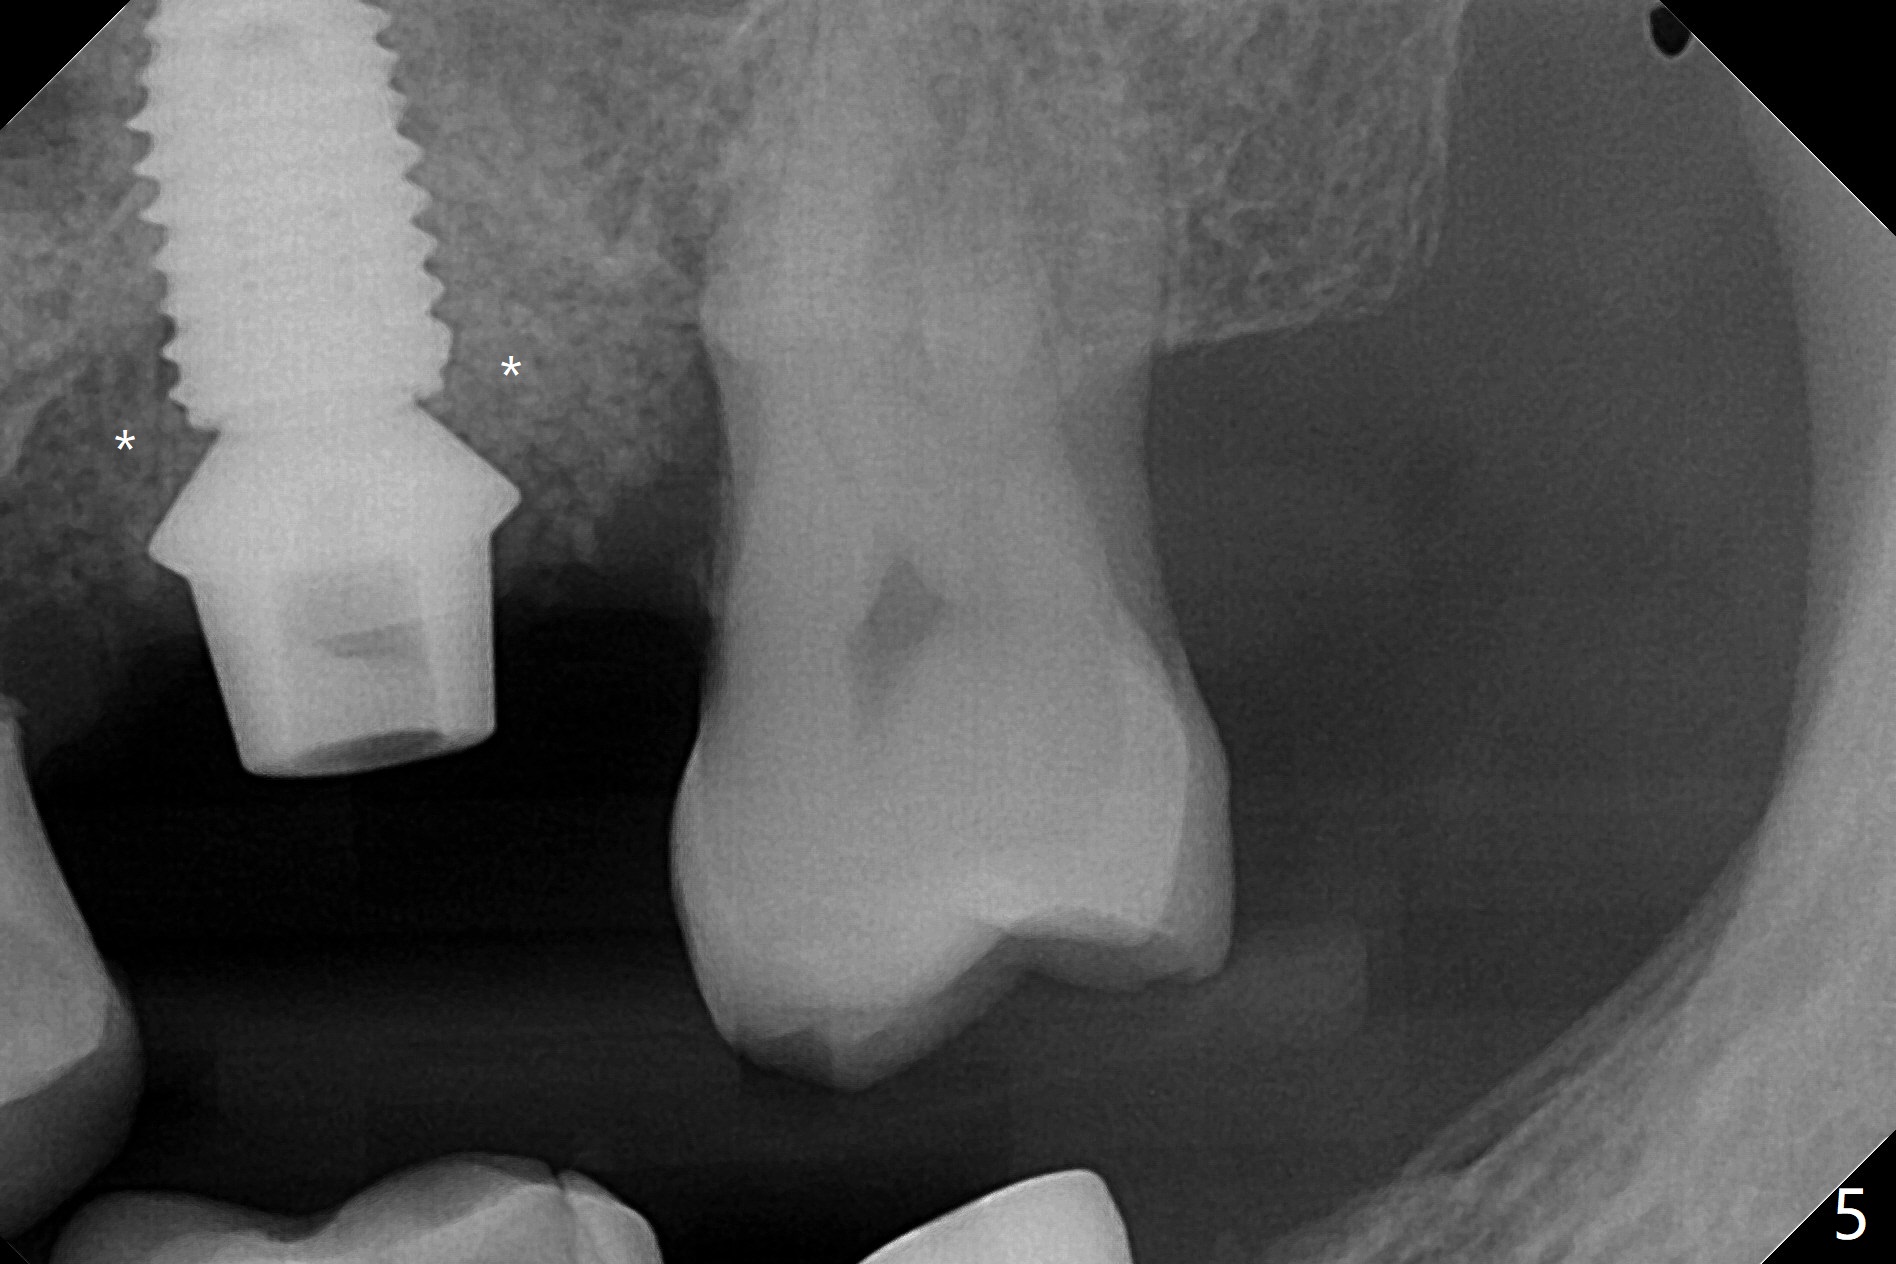

72岁男14号牙腭侧根尖接近上颌窦(图一,二:P),牙齿拔除后,根尖对刮治敏感,冲洗后,开始导板钻洞,圆钻穿透窦底,放置粘性骨粉和报废植体提升(图三:箭头)。放置小张PRF和骨粉(图四:箭头),植入正式植体,基台和骨粉(图五:*),最后覆盖PRF(图六),为了防止骨粉从邻牙牙龈沟(>)丢失,覆盖树脂敷料。基台和前后邻牙使树脂敷料术后一周巍然不动(图七:A)。术后一个月撤除树脂敷料,牙槽窝已经愈合(图八)。再过两周牙槽窝上皮好像进一步成熟(图九),然后塞入一个龈线,制备临时牙冠。